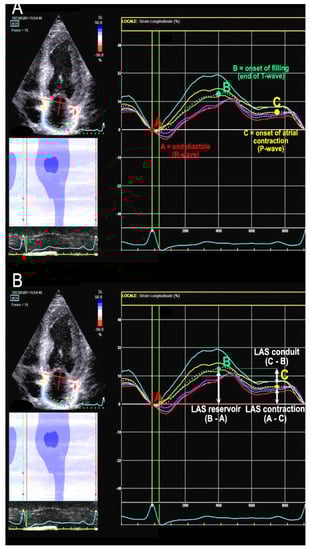

Phasic strain calculation involves calculating the deformation of atrial wall during three phases: reservoir strain (LASr), conduit strain (LAScd), and contraction strain (LASc). LASr, always positive, is calculated as the difference between the strain value at the curve peak and the end-diastolic value. LAScd, always negative, is calculated as the difference between the strain value at the onset of atrial contraction (p-wave) and the peak value (in atrial fibrillation (AF) patients, LAScd has the same value as LASr but with a negative sign) [15]. LASc is calculated from the difference between the strain value at end-diastole (R-wave) and the value at the onset of p-wave. It always exhibits a negative value and only occurs in sinus rhythm. See Figure 1 for details.

Figure 1. Left atrial strain (LAS) assessment. The white dotted line represents the average of the curves of the six atrial segments. (A): reference points for atrial function phases in relation to ECG waves and cardiac cycle. (B): here it is shown how to calculate the three LAS values from the reference points.